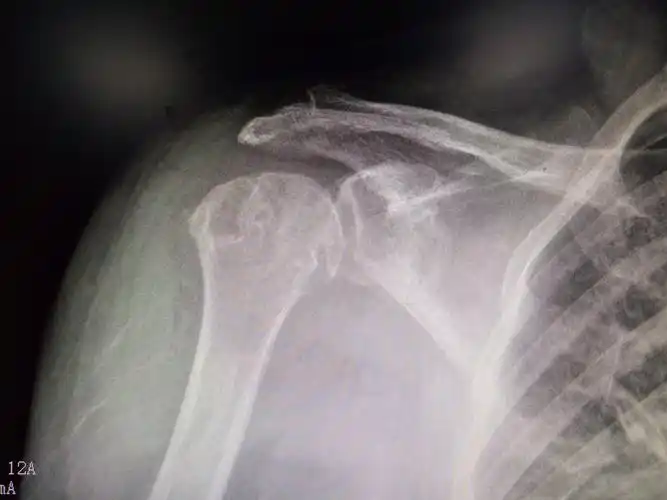

术前可见右肩关节脱位,喙突与锁骨间隙增大.

其它 肩关节前上脱位病例 写美篇现在自诉右肩关节脱位,前屈上举困难.